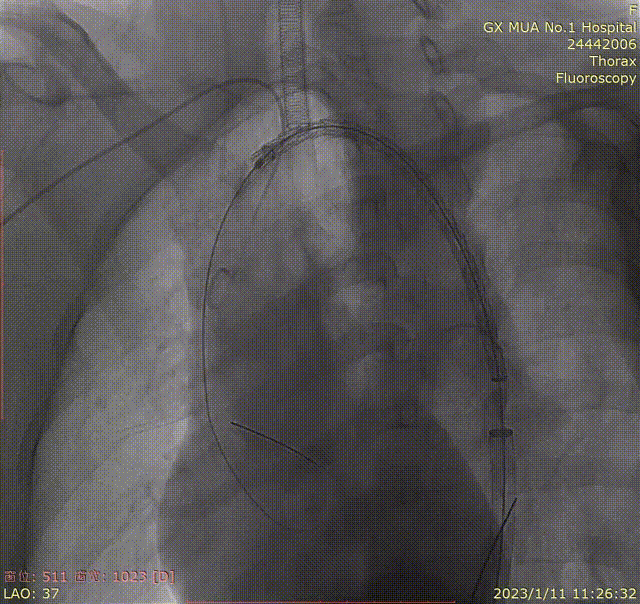

双导丝置入长鞘过弓

第一导丝用于平滑弓形角度,并稳定血管形态,第二导丝保持长鞘的前进方向与前者同轴。

即使有双导丝加持,长鞘在过弓的时候还是会遇到阻力,此时不要蛮力推进,可以轻微抖动回撤导丝,卸除一部分应力再尝试推进,切勿追求一步到位。

gore医疗怎么样「胸有乾坤」化险为夷,通险畅机——GORE® TAG® 胸主动脉覆膜支架治疗累及异形弓部动脉瘤_https://www.jmylbn.com_新闻资讯_第15张

单导丝塑形

gore医疗怎么样「胸有乾坤」化险为夷,通险畅机——GORE® TAG® 胸主动脉覆膜支架治疗累及异形弓部动脉瘤_https://www.jmylbn.com_新闻资讯_第16张

双导丝导引弓部成型

gore医疗怎么样「胸有乾坤」化险为夷,通险畅机——GORE® TAG® 胸主动脉覆膜支架治疗累及异形弓部动脉瘤_https://www.jmylbn.com_新闻资讯_第17张

引导鞘过弓